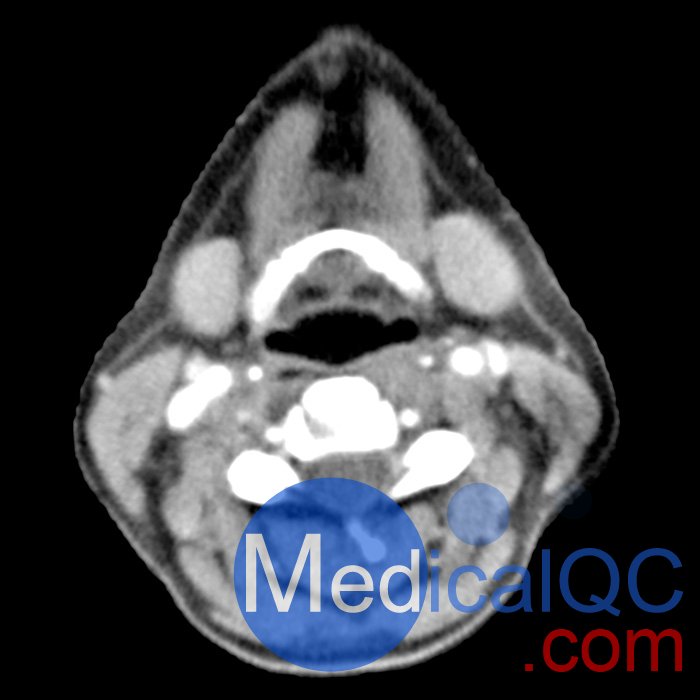

phantomX頭頸部模型,phantomX頭部模體是根據(jù) CT 數(shù)據(jù)制造的,包括所有組織的解剖細(xì)節(jié)。它經(jīng)過(guò)優(yōu)化,可在計(jì)算機(jī)斷層掃描中以 120 kVp 成像提供真實(shí)的衰減值,對(duì)應(yīng)于 73 keV 的平均光譜能量。可根據(jù)要求校準(zhǔn)其他光譜能量。

體模的尺寸和設(shè)計(jì)可能會(huì)發(fā)生細(xì)微變化。體??梢宰鳛橐患綌M人體?;蛞越孛嬖O(shè)計(jì)的形式提供。可以包括病理特征(例如,腫塊、血管病變)。